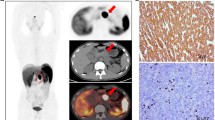

68Ga-DOTATOC PET/MRI detected liver metastasis in 3/16 patients (19%); specifically, all 3/3 patients presented intense focal 68Ga-DOTATOC uptake in correspondence of the pathological liver findings on diagnostic MR images. In Fig. 3, a representative case of a patient with liver metastases detected both on PET and MRI images is reported.

68Ga-DOTATOC PET/MRI performed for PanNET staging. A 60-year-old patient underwent 68Ga-DOTATOC PET/MRI. 68Ga-DOTATOC PET/MRI showed intense uptake in correspondence of the pancreatic tail (a: axial Lava Flex MRI; b: axial 68Ga-DOTATOC PET, cyan blue arrow; c: axial 68Ga-DOTATOC PET/MRI, cyan blue arrow) and two pathological uptakes in correspondence of the VI (b and c: red arrow) and IV hepatic segments (d: axial Lava Flex MRI; e: axial 68Ga-DOTATOC PET, red arrow; f: axial 68Ga-DOTATOC PET/MRI, red arrow); g: histological section, haematoxylin and eosin stain of the primary PanNET (G2; Ki67: 5%); h: histological section, haematoxylin and eosin stain of a lymph node entirely replaced by the tumour